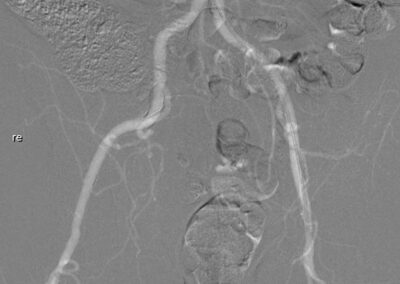

Sie möchten sich einen ersten Überblick über unser Produkt, dem CO2 Injektor Inspect 3005R verschaffen?

Nachfolgend haben wir eine Reihe Infomaterial über denKontrastmittelinjektor (Kontrastmittelpumpe) für die CO2 Angiographie zusammengestellt.

Wahl geeigneter Katheter und Katheterpositionen angepasst an Fragestellung und Gefäßgebiet mit Möglichkeit zur selektiven Darstellung

Wahl eines für die spezifische Untersuchung geeigneten Kontrastmittels

(z.B. jodhaltiges Kontrastmittel vs. CO2)

Ausreichende Kontrastmittelmenge und Kontrastmittel-Konzentration sowie geeigneter Kontrastmittel-Fluss (ggf. maschinelle Injektion)

Nachfolgend haben wir für sie eine Reihe Publikationen / Links über das Thema CO2 Angiographie zusammengestellt.

Es gibt aktuell über 450 Publikationen zum Thema CO2 Angiographie.